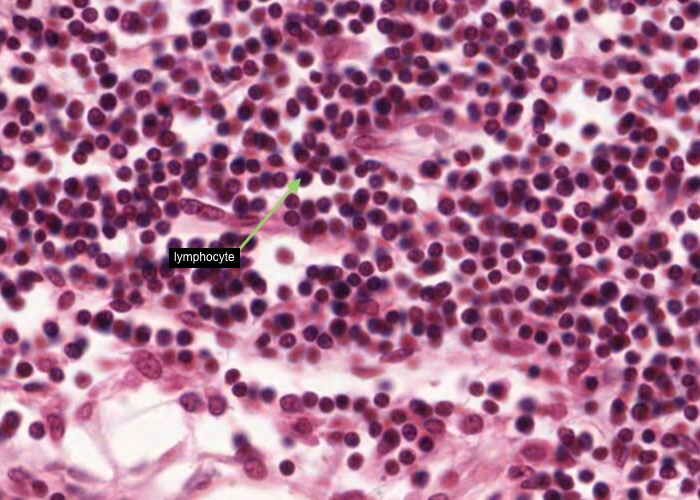

Tonsils house vast numbers of lymphocytes. These cells are drawn in from the blood through tall postcapillary venules, similar to those you will see later in the lymph node.

The lymphocytes wander throughout the mucosa waiting to be stimulated by antigens that diffuse in from the decaying debris in the crypt. Many invade the epithelium, so much so that, in some places, you have trouble recognizing the epithelium at all. At high magnification such epithelium looks like dense aggregations of lymphocytes (each with dark, circular nucleus) with the anomalous large pale nucleus (of each of the epithelial cells) scattered among them.

Finally there are substantial numbers of small lymphocytes each with a circular, dark-stained nucleus.